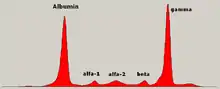

La principale conséquence du myélome est la présence d'une très grande quantité d'immunoglobulines dans le sang. Ces immunoglobulines sont des protéines, qui se manifestent par :

- un pic dans la zone des gamma-globulines à l'électrophorèse des protéines du sérum dans les formes à chaîne complète. L'immunofixation permet de prouver le caractère monoclonal du pic (c'est-à-dire dérivant d'un même clone tumoral de plasmocytes) . Dans les formes à chaînes légères, on observe une hypogammaglobulinémie, la quantité de chaînes légères n'étant quasiment jamais suffisante pour faire apparaître un pic monoclonal visible.

On retrouve aussi un excès de protéines dans les urines ; cette protéinurie est constituée de chaînes légères des immunoglobulines monoclonales, aussi appelées protéine de Bence-Jones. L'immunoélectrophorèse ou l'immunofixation des protéines urinaires détermine le type de chaîne, kappa ou lambda. Ce pic est décelé dans les bêtaglobulines.